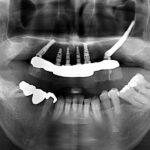

手術前口腔内

手術後パノラマX線写真